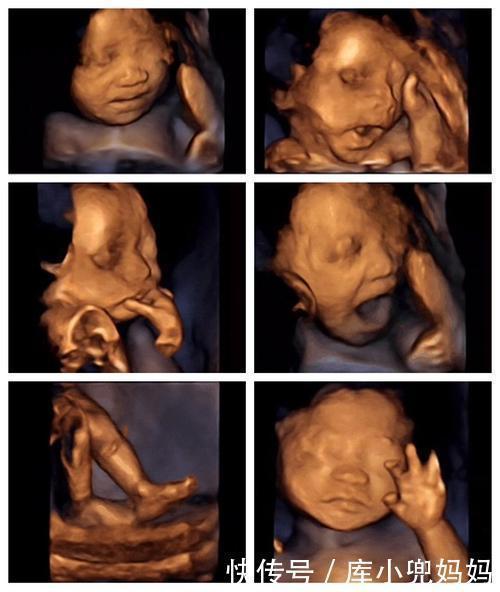

四维彩超

做四维最折磨人的是做了很多次,有时候宝宝不配合就是不动,或者是观察角度的问题,会出现某些部位看不清楚或是不可见的情况,。外出散步、爬楼梯、吃东西、拍肚子,各种招数都用尽了,胎儿就是稳坐中军帐不动一动。害得有些孕妈还要第二天或者再等一周再去,最是折磨人。这项检查又不能稀里糊涂地凑合,还要看清楚整个结构才能放心,迫不得已还得再去。